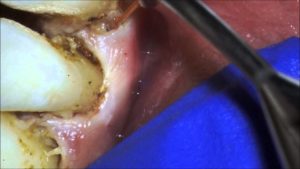

upper lip frenectomy and gingivectomy

Frenectomy and Laser Gum Surgery on Advanced Periodontitis